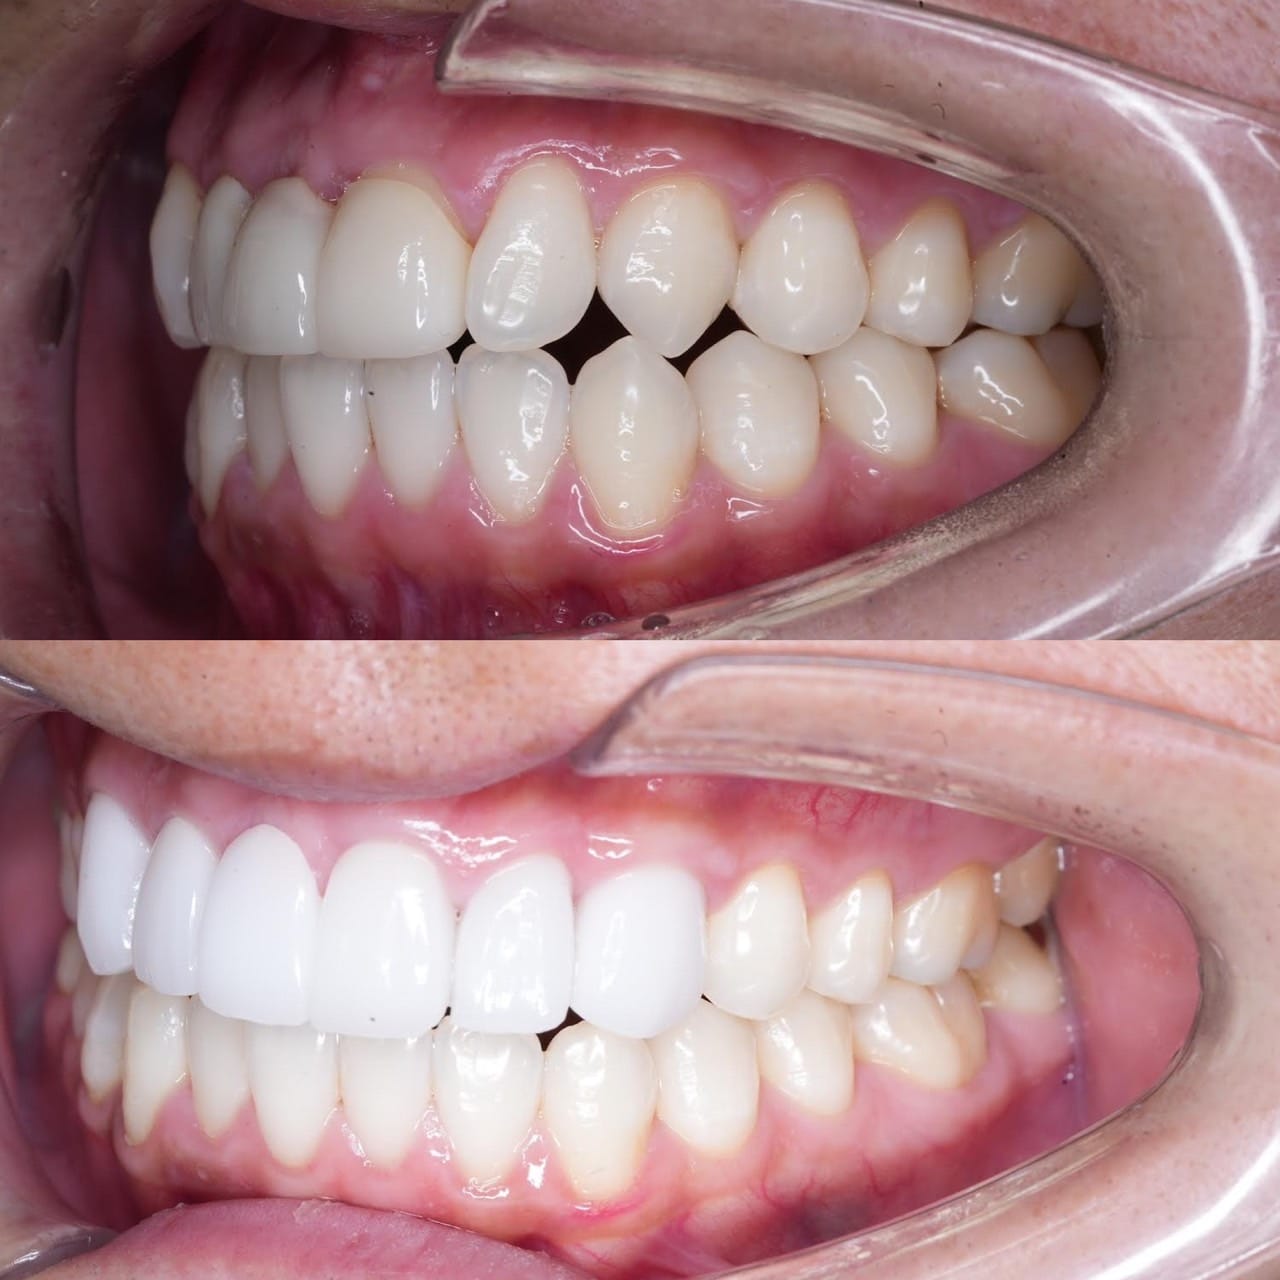

前医でインプラントの埋入角度が悪く、インプラント周囲炎になってしまった患者様の症例です。

インプラントが虫歯になることはありませんが、インプラント周囲炎というインプラントの歯周病にはなります。

インプラント周囲炎の主な原因は汚れ(菌)と力です。このように斜めに埋入されているインプラントは、真っ直ぐ埋入されているものに比べて汚れも溜まりやすく、噛む力も斜めにかかってしまうため、インプラント周囲炎になるリスクが大幅に高くなります。

この患者様は内側の骨が大幅に溶けてしまっていたので、前のインプラントを撤去して、骨を再生させると同時にインプラントを正しい位置と角度で埋入し直しました。溶けてしまっていた骨が治っていることもレントゲンでご確認いただけるかと思います。

インプラントは「どこの位置にどのような角度で入れるか」によって、一生使い続けられるかどうかの期待値が大きく異なります。値段だけを基準にクリニックを決めるのではなく、信用できる歯医医師と治療を進めることをお勧めします。